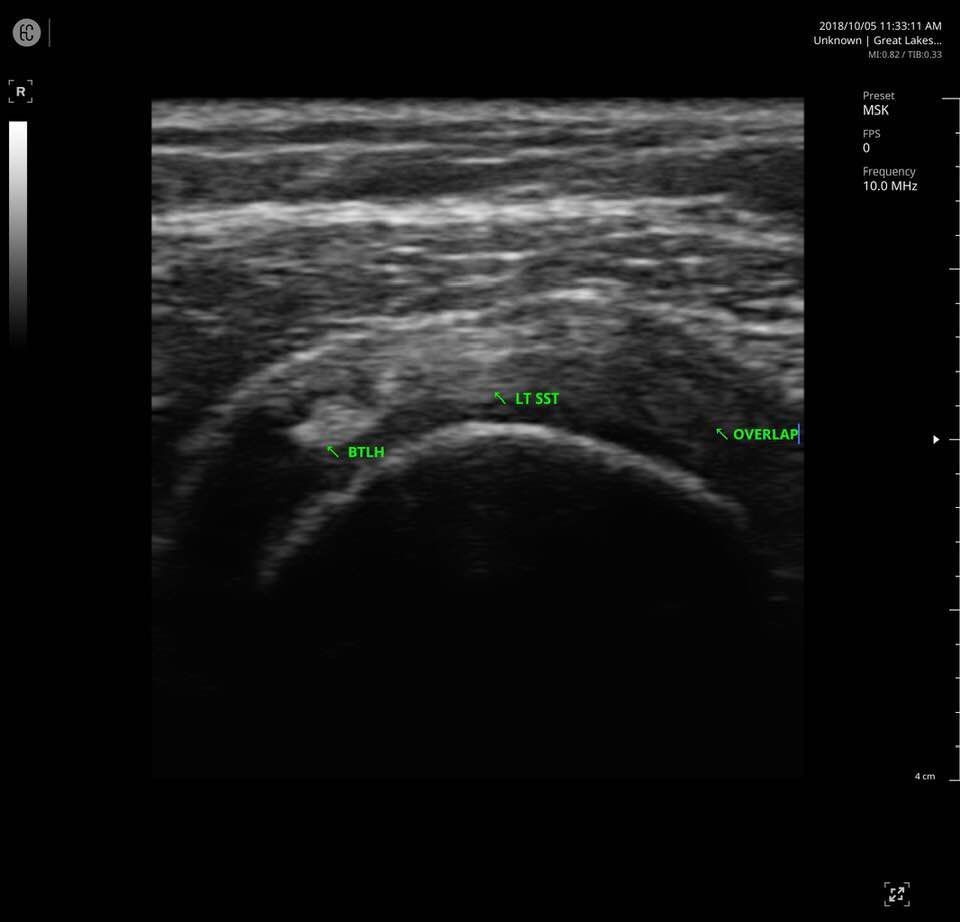

The SONON 300L transducer has cutting-edge technology and its software, combined with a proprietary sensor, turns any mobile device into a mobile ultrasound monitor with the same image quality and knobology as a traditional US machine. Software includes individual preset settings for your most common test.

- MSK

Specifications for SONON 300L:

- Multi-frequency: 5MHz 7.5MHz 10MHz

- Depth: max 10cm

- Field of View: 40mm